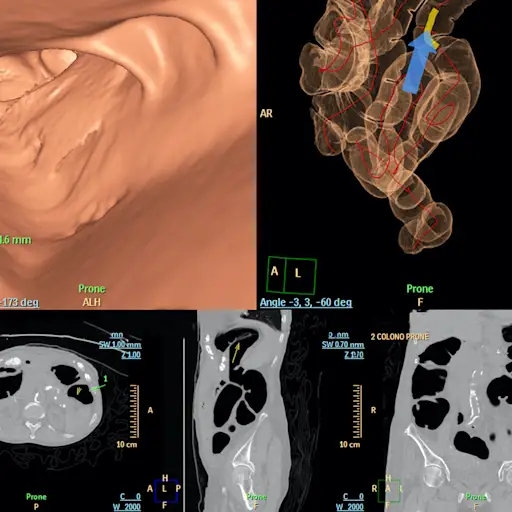

虽然没有一个尺寸适合的核心癌症治疗,但行动的过程通常取决于其阶段。“结肠直肠癌治疗是由癌症阶段引导的,”西雅图癌症联盟医疗肿瘤科医生和华盛顿大学肿瘤科副教授的医学肿瘤科医生。“该阶段由成像 - 例如CT扫描,结肠镜检查,MRI和病理学的组合来确定。(以及一如既往地,您的提供商将成为您的进入资源,以了解您最可行的治疗方案。)

如果您的癌症被归类为阶段肿瘤,这意味着它位于您的结肠上的一个特定点,并没有在您的身体中的任何其他地方传播。科恩博士解释说,在这种情况下,医生通常会在结肠镜检查期间进行简单的息肉去除。如果癌症完全被删除,则此时可能不需要进一步的干预。但是,您的医生将希望密切监视该地区,以确保您在未来几个月甚至几年内保持无癌症。